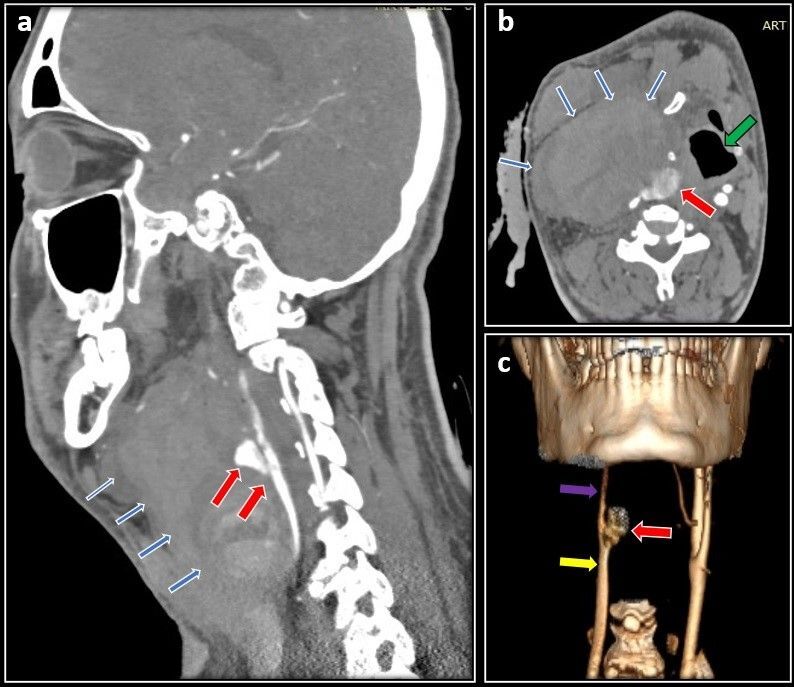

A 47-year-old male presented with a right-sided Shamblin type 2 carotid body tumor measuring 5*5 cm. After preoperative embolization, a sub adventitial resection of the tumor was done. He was discharged after postoperative day 5 and presented again to emergency 10 days later with a bleeding pseudoaneurysm at the surgical site causing dysphagia and dyspnea. He was taken for emergency exploration of the surgical wound and, intraoperatively, it was observed that the proximal ends of the internal carotid artery and external carotid artery close to the bifurcation were forming a pseudoaneurysm, 1 cm distal to the common carotid artery. The external carotid artery was ligated and a common carotid to internal carotid artery bypass was done with a reversed saphenous vein graft. He recovered well in the postoperative period and was discharged on day 7. Pseudoaneurysm formation following carotid body tumor resection is extremely rare and has only been reported thrice in the literature.

Abstract Image